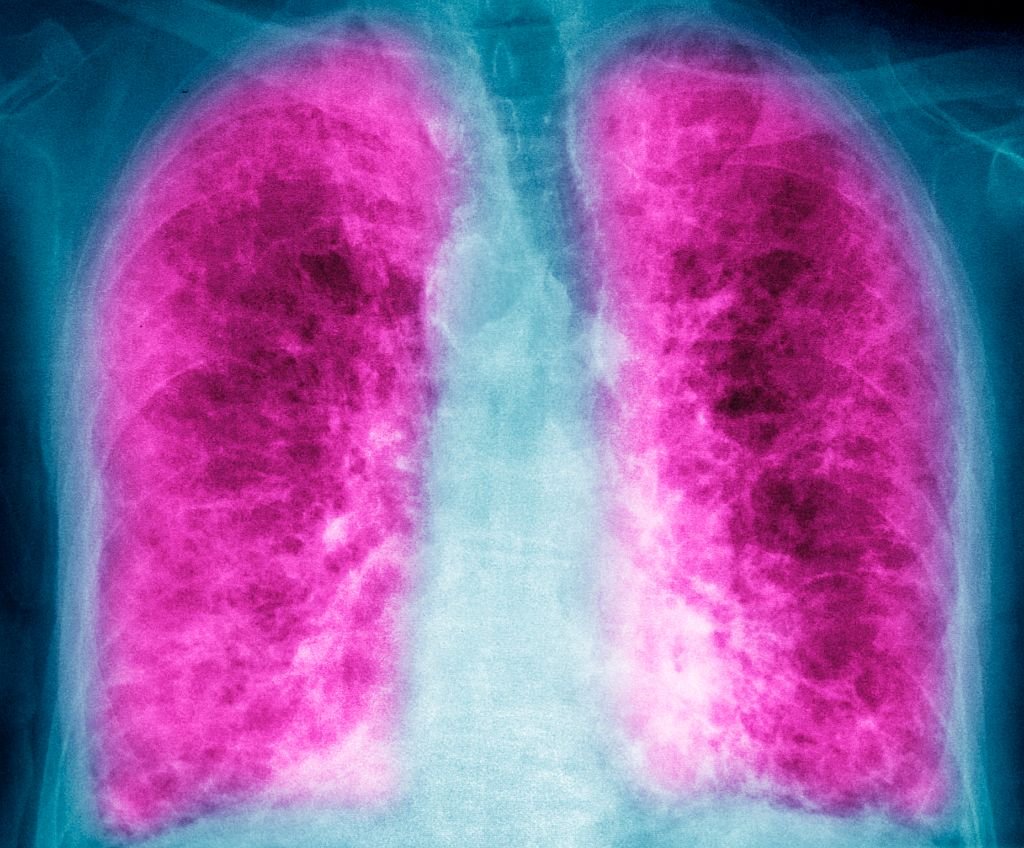

The few drugs available for lung disorders that cause scarring of the organ are pills that circulate throughout the body. Avalyn Pharma is aiming for a better effect with inhalable medicines, and the company now has $300 million to show that benefit through ongoing clinical trials.

Boston-based Avalyn is developing drugs for two types of pulmonary fibrosis, a disorder that leads to inflammation and the development of scar tissue, a pathological process called fibrosis. In idiopathic pulmonary fibrosis (IPF), the cause of fibrosis is unknown. In progressive pulmonary fibrosis (PPF), the cause can be attributed to something such as an autoimmune disease or exposure to allergens.

While the oral drugs aren’t cures for pulmonary fibrosis, they can slow its progression. But one problem with these pills is the wide range of side effects they cause as these small molecules circulate throughout the body. Nausea and diarrhea are common. In the Ofev studies, cardiovascular problems were reported. Side effect and tolerability issues lead many patients to reduce or interrupt dosing. In the IPO filing, Avalyn said just 30% of IPF patients are actively treated with antifibrotic medications and 50% of patients discontinue them within a year of starting treatment.

Avalyn drug AP01 is an inhalable version of pirfenidone; AP02 is an inhalable formulation of nintedanib. A third Avalyn drug, AP03, is an inhalable fixed-dose combination of pirfenidone and nintedanib. These drugs are administered via a proprietary nebulizer device. Inhalable formulations enable lower dosing than what’s required for oral administration, which should further reduce side effect and tolerability problems.

“By delivering drugs directly to the lungs, our approach is designed to fundamentally improve the benefit-risk profile of antifibrotic therapy by achieving higher drug concentration at the site of disease while substantially reducing systemic exposure,” Avalyn said in the filing. “We believe this lung-targeted delivery strategy enables sustained long-term treatment, addressing key limitations of existing systemic therapies and supporting better treatment adherence and long-term disease management for patients with pulmonary fibrosis.”